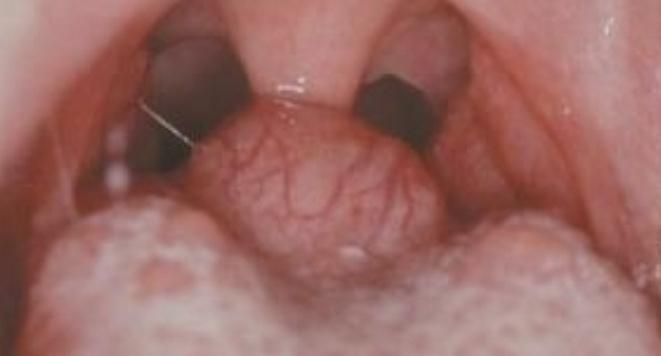

lingual thyroid

thyroid gland develops __ and descends into the neck by __

3-4 wks of life; 7th wk

__ % of ectopic thyroids are in this position

90

lingual thyroid is more common in

females (7:1)

In cases of lingual thyroid, this is the only thyroid tissue __% of the time

70

Is tx needed for lingual thyroid?

no tx needed unless a problem develops (adenoma or adenocarcinoma)